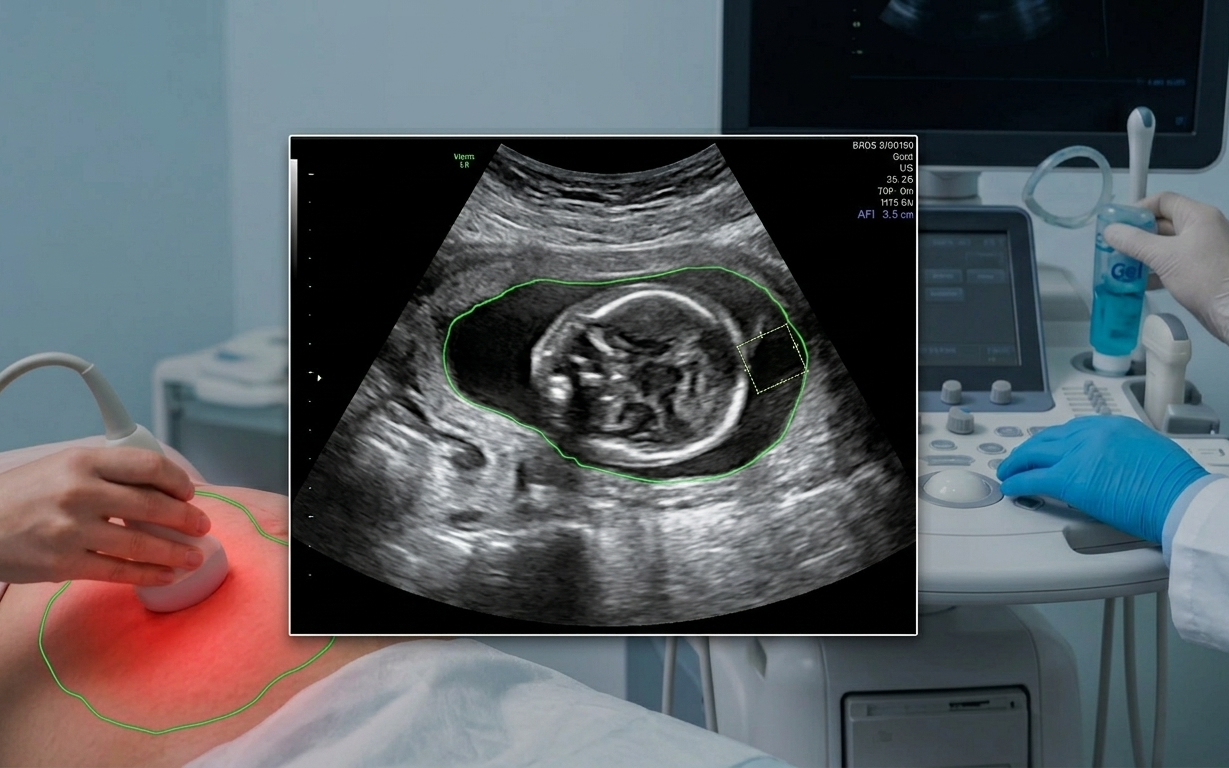

Các bác sĩ sẽ giám sát chặt chẽ sức khỏe tim mạch trong các buổi khám thai định kỳ.

Những điều chỉnh này là thiết yếu cho một thai kỳ khỏe mạnh nhưng việc theo dõi là rất quan trọng. Các bác sĩ sẽ giám sát chặt chẽ các chỉ số tim mạch trong các buổi khám thai định kỳ, cho dù mẹ bầu có bệnh lý tim mạch tiềm ẩn hay có nguy cơ gặp các vấn đề tim mạch liên quan đến thai kỳ.

Chăm sóc tiền sản giúp theo dõi sự tăng trưởng và phát triển của em bé nhưng đó cũng là cách tốt nhất để giám sát trái tim và sức khỏe tổng thể trong suốt thai kỳ. Bác sĩ sẽ theo dõi huyết áp mỗi lần khám và có thể yêu cầu xét nghiệm máu để giúp đánh giá các yếu tố nguy cơ, chẳng hạn như thiếu máu hoặc những thay đổi trao đổi chất ảnh hưởng đến sức khỏe tim mạch.